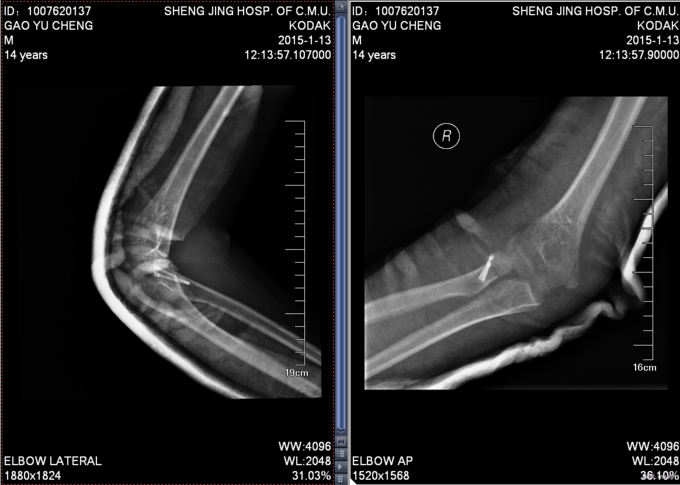

患者入院后肘关节肿胀明显,消肿约1周后,查无明显手术禁忌症后,全麻下行左桡骨小头骨折空心钉内固定术。术后给予患者石膏固定,定期换药,14天后拆线出院,建议石膏固定4周。